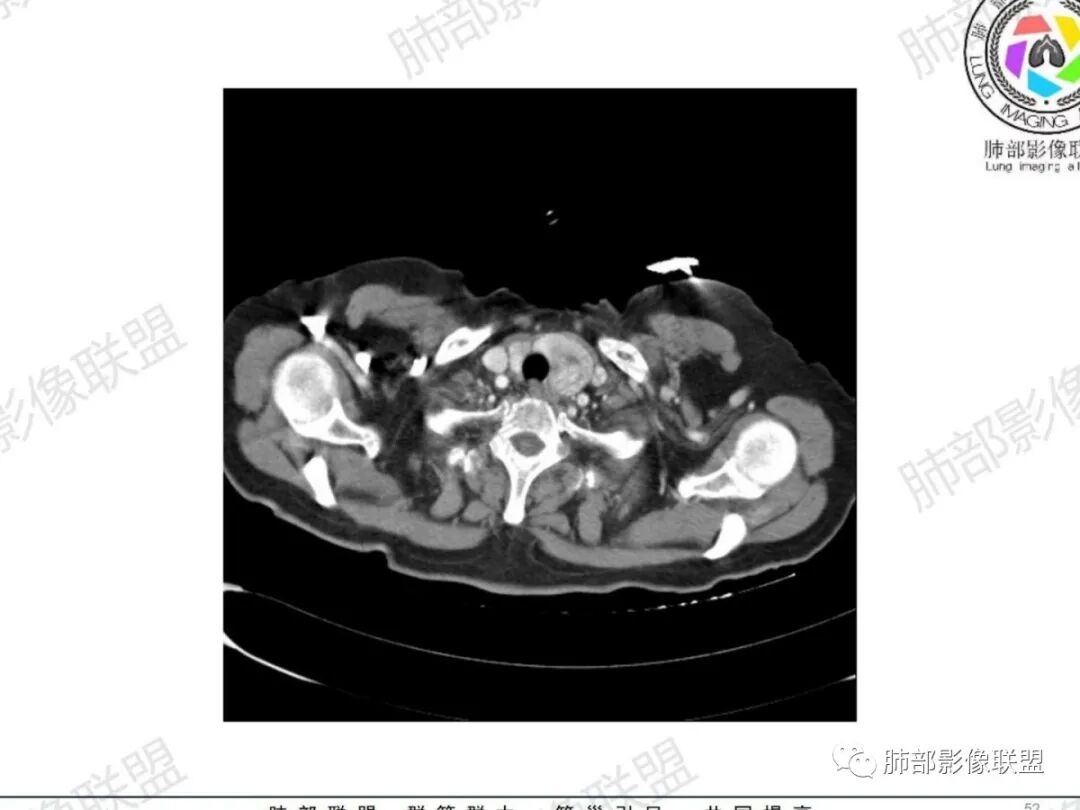

从病史提示:甲状腺占位、气管占位、肺部炎症

甲状腺左叶结节边界不太清楚

气管右后壁占位,平扫密度稍低于肌肉

甲状腺结节边界不太清楚,但是窗宽窗位不太理想,需要调至最佳状态观察才合适

病理类型:甲状腺如果是恶性的,还是要警惕转移瘤;原发的:倾向于恶性,老年女性,表面光滑, 鳞癌几率比较低;腺样囊性癌确实要考虑